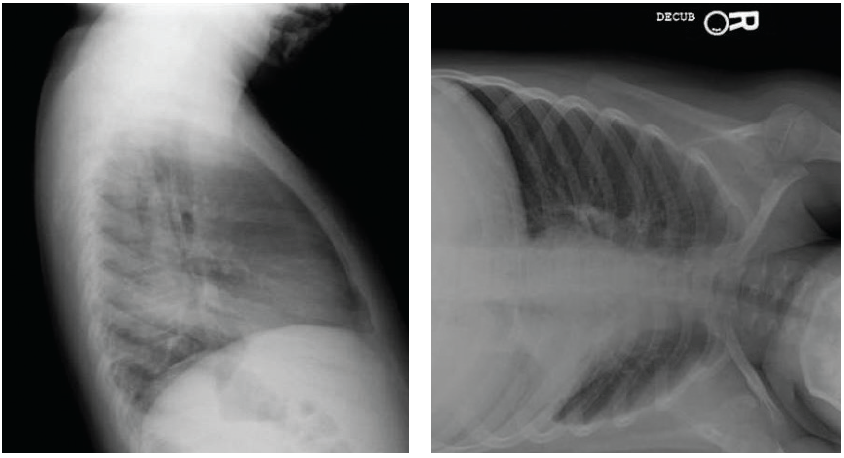

Chest radiographs taken in our ED were remarkable for an opacity in the left lower lobe on posteroanterior view (Figure 3) and lateral view (Figure 4), with significant hyperinflation of the boy’s right lung. Left lateral decubitus view showed an incomplete collapse of the left lung (Figure 5).

Figure 5. Left lateral decubitus radiograph of the boy’s chest showing incomplete left lung collapse. The plastic end of a mechanical pencil later was removed from the left secondary bronchus.